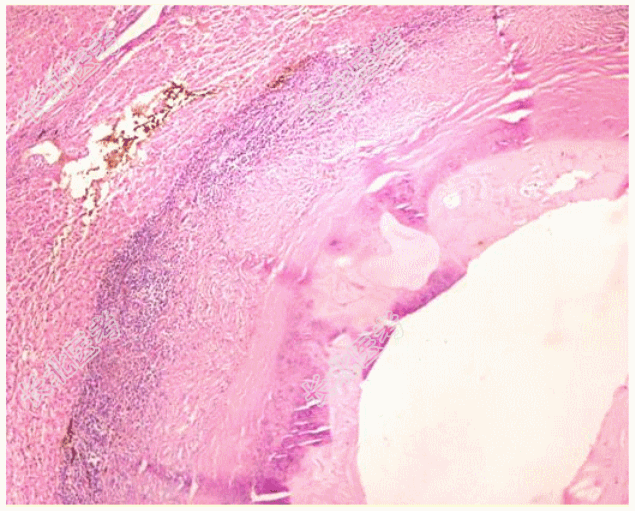

- 简答题1、手术切除标本光镜观察如下图,最可能的诊断是?